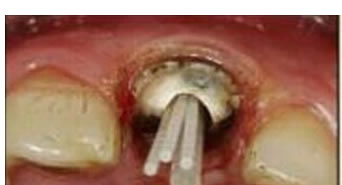

圖3:根管內(nèi)殘留物

圖4:超聲去除根管殘留物。

根管壁殘留物的存在直接影響著纖維樁的粘接和固位,是纖維樁脫落的主要原因之一。由于圓形的根管鉆和根管形態(tài)不完全一致,終鉆預備完成后大多情況下樁道側(cè)壁會有不同程度的牙膠和封閉劑等殘留物附著(圖 3)。因此,建議X線檢查根管預備情況,選用超聲潔牙機更換較細工作尖進入根管,徹底去除樁道根管壁上附著的殘留物(圖4)。使用根管銼去除殘留物時,很難清除干凈;禁止使用牙膠溶劑如丁克除、氯仿等有機溶劑去除殘留物,以免破壞根尖區(qū)牙膠的封閉,或有機溶劑粘附于根管壁形成蠟膜而影響粘接。